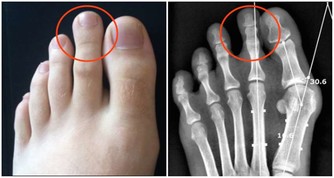

腳上有開放性潰瘍腳上的開放性潰瘍會令人感到難以置信的疼痛,需要讓醫生盡快檢查,因為它們可能是一種名為主髂動脈閉塞性疾病的心髒病的跡象,即主動脈被堵塞了。這種病會導致缺血,使流向組織的血液和氧氣供應減少。缺血可能導致足部組織破裂,形成開放性潰瘍。

腳趾疼痛如果你經常在沒有明顯原因的情況下腳趾疼痛,並且在休息時注意到腿部寒冷或麻木,這也是主髂動脈閉塞性疾病的一個跡象。